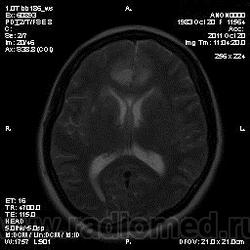

Эта же пациентка... Июль 2011 года....

В анамнезе есть зацепки на энцефалит?Мне ни разу не встречался, поэтому умничать не буду.

А здесь вариант Арнольда-Киари+ платибазия к тому же (?)

мне кажется больше похоже на диффузную глиальную опухоль. Для герпетического нехарактерна локализация и характер контрастирования. Хотя конечно нет правил без исключений..

Евгений Второй, а медиобазальные отделы височных долей - по-моему излюбленная локализация герпетических энцефалитов... Да мне кажется, что серое и белое вещество в равной степени вовлечено в процесс...

Арнольда-Киари можно указать, но вы же понимаете, что он меркнет на фоне основной патологии....

а медиобазальные отделы височных долей - по-моему излюбленная локализация герпетических энцефалитов..

Абсолютно согласен, просто у меня не все картинки раньше загрузились и показалось, что все изменения в лобных долях и базальных ядрах. Снимаю свои возражения.